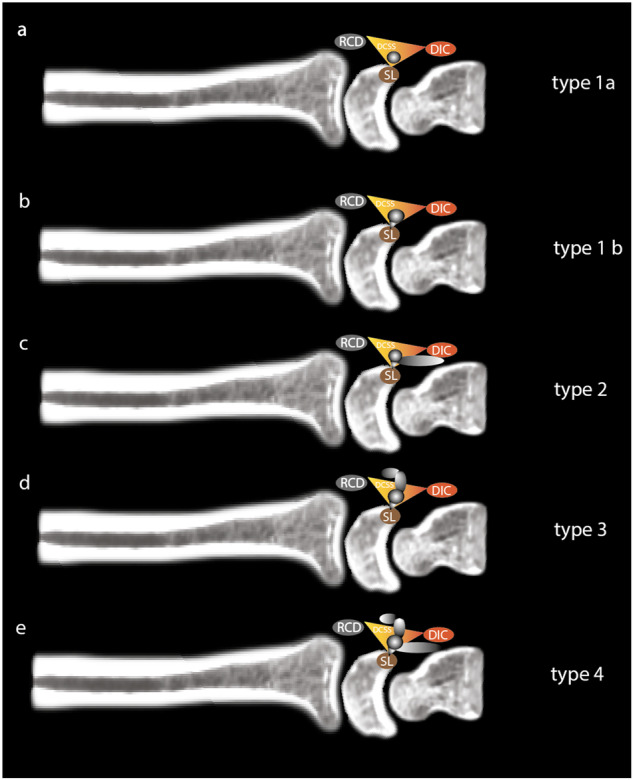

We would draw attention to the importance of preoperative MRI in these cases. The use of high-field MRI should provide a precise description of the anatomy of the cyst, its relationship with neighboring structures, in particular the DCSS and DIC, which must be preserved during surgery, and above all the pedicle at the origin of the cyst. The latter should be resected at the same time as the cyst [3]. An adaptation of Guérini’s classification, considering current anatomical knowledge incorporating DCSS, SL pedicle recognition, and location of the cyst in relation to the DIC, would probably be beneficial for anatomical assessment prior to any surgical management, which is why we are proposing a new radiological classification (see Fig. 6). Inter-observer agreement when using this classification was substantial. Using this new classification, we distinguished between very small cysts all located exclusively in the DCSS for which we visualized the pedicle (1b) and those for which the pedicle was not visualized (1a) around 70% n = 72/103 and 30% n = 31/103, respectively. This systematic description of whether or not the pedicle has been visualized by the radiologist using this new classification is therefore essential information to be provided to the surgeon prior to any surgical management, the aim being to complement without replacing arthroscopic observation. In addition, particular attention must be paid to the integrity of the SL and the DCSS, whose lesions will modify the surgical management technique with the addition of a capsulo-ligament repair [21].

Fig. 6.

Classification of mucoid cysts of the dorsal aspect of the wrist at the expense of the DCSS and the SL ligament. a Type 1a: Cyst originating in the DCSS with no visible pedicle in the SL; b type 1b: Cyst originating in the DCSS with visible pedicle in the SL; c type 2: Cyst originating in the DCSS with extension under the DIC; d type 3: Cyst originating in DCSS extending dorsally to RCD; e type 4: Complex cyst originating in DCSS with extension under DIC and dorsally to RCD. DIC, dorsal intercarpal ligament; RCD, radio-carpal ligament; DCSS, dorsal capsular scapholunate septum; SL, scapholunate ligament